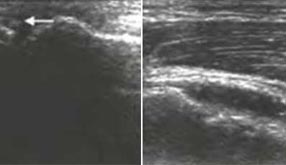

肌骨超声(musculoskeletal ultrasound,MSUS)技术是通过高频超声(3~17Hz)扫描提供优异的临床图像,以清晰显示肌肉等软组织层次关系及其内部机构来诊断肌肉骨骼系统疾病的新型超声检查技术。通过肌骨超声,医生可以分辨毫米级以下动态的这些组织结构肌肉、肌腱、韧带、关节囊、关节面及周围神经等浅表软的毗邻关系、形态大小、结构纹理、血流分布,从而获取这些组织器官的解剖变异、炎症、退行性病以及创伤等病变的全方位信息,从而对疾病进行精准评估。

动态观察滑膜血流信号,早期监测RA活动

清晰显示滑膜异常形态,定量评估RA炎性